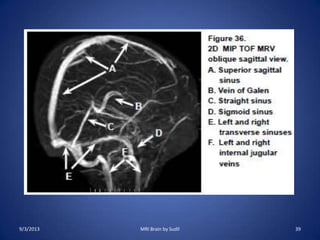

MR Venography (MRV)

• Indications:

–Evaluation of intracerebral veins and

intradural venous sinuses for thrombosis

• Sequences

– Routine brain protocol

– PC images in the sagittal plane (for superior sagittal

sinus) and in the axial plane (for transverse sinus).

– 2D TOF in the sagittal and coronal plane through whole

head.

• The coronal sequence must include the confluence of

sinuses in posterior part of the head.

• The coronal TOF acquisition can lead to artefactual loss of

signal in transverse sinuses due to in plane flow. An oblique

transverse scan obtained in plane of transverse sinus help

evaluate such an artifact.

• For evaluation of patient suspected of having venous

thrombosis, MRV is done along with stroke protocol.